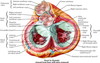

Defining the mediastinum

Cross-sectional midline of the mediastinum defined from the sternal angle anteriorly to the T4 vertebrae posteriorly

Above this is the superior mediastinum

Below this is the inferior mediastinum

The inferior mediastinum is divided into the anterior, middle and posterior divisions

Anterior: in front of fibrous pericardium

Middle: pericardium and great vessels

Posterior: from posterior surface of pericardium to T5 - T12 vertebral bodies

Divisions of the inferior mediastinum

The inferior mediastinum is divided into the anterior, middle and posterior divisions

Anterior: in front of fibrous pericardium

Middle: pericardium and great vessels

Posterior: from posterior surface of pericardium to T5 - T12 vertebral bodies

Fusions of the pericardium

Conical fibrous sace containing the heart and roots of the great vessels

Apex is fused with the adventitia of the great vessels

Base is fused with the central tendon of the diaphragm

Anterior relations of the pericardium

(4)

Body of the sternum

Attached by the sternocardial ligaments

3rd - 6th costal cartilages

Anterior borders of the lungs

Posterior relations of the pericardium

(6)

- Oesophagus

- Descending aorta

- T5 - T8 verebrae

- Roots of the lungs

- Mediastinal pleural

- Phrenic nerve